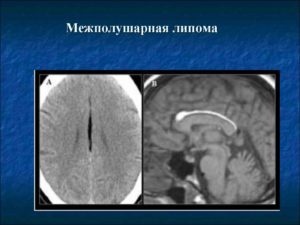

Новообразование безболезненное, подвижное, мягкое по консистенции. В зависимости от места локализации различают межполушарную и липому межполушарной щели. Опухоль образуется только в 2 отделах внутричерепной коробки, редко в цистерне четверохолмия.

Межполушарный жировик формируется в мозолистом теле у детей или взрослых. Во время диагностических мероприятий часто обнаруживается скопление нескольких опухолей.

Пациентов беспокоят зрительные и звуковые галлюцинации, неконтролируемые движения конечностей, заторможенность, увеличение выработки гормонов гипофиза.

- Межполушарная липома образуется в мозолистой ткани головного мозга. Чаще всего встречается множественная форма жировика. Опухоль препятствует нормальному функционированию мозжечка, провоцирует нарушения человеческого поведения и когнитивных функций. Жировик провоцирует возникновение массивных психических расстройств, поражая оба полушария мозга. На фоне расстройства наблюдается появление галлюцинаций, расстройств памяти вплоть до прогрессирующего слабоумия.

- Липома межполушарной щели головного мозга обнаруживается случайно при полном профильном обследовании человеческого организма, так как на начальной стадии развития скрытна. Большинство людей могут жить с опухолью мозга на протяжении многих лет и не подозревать о патологии. Увеличиваясь в размерах, липома препятствует нормальному кровообращению внутричерепной области, что чревато частыми потерями сознания, головокружением, тошнотой и головными болями. Мутированная ткань жировика неблагоприятно влияет на центральную область мозга, вызывая зрительные и слуховые галлюцинации, поведенческие нарушения и дисфункцию моторики. Жировик давит на центральную нервную систему, нарушая циркуляцию спинномозговой жидкости. Головной мозг человека считается самым опасным местом для локализации для жировика, так как вызывает расстройства психики и, распространяясь на область гипофиза, может привести к параличу.